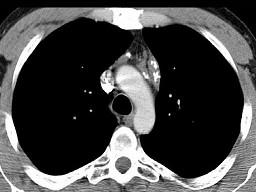

问题 21岁,女,颈部淋巴结肿大,无压痛,请结合CT检查选出最可能的诊断 ( )

选项 A、转移性淋巴结肿大 B、间皮囊肿 C、淋巴结核 D、结节病 E、淋巴瘤

答案 E